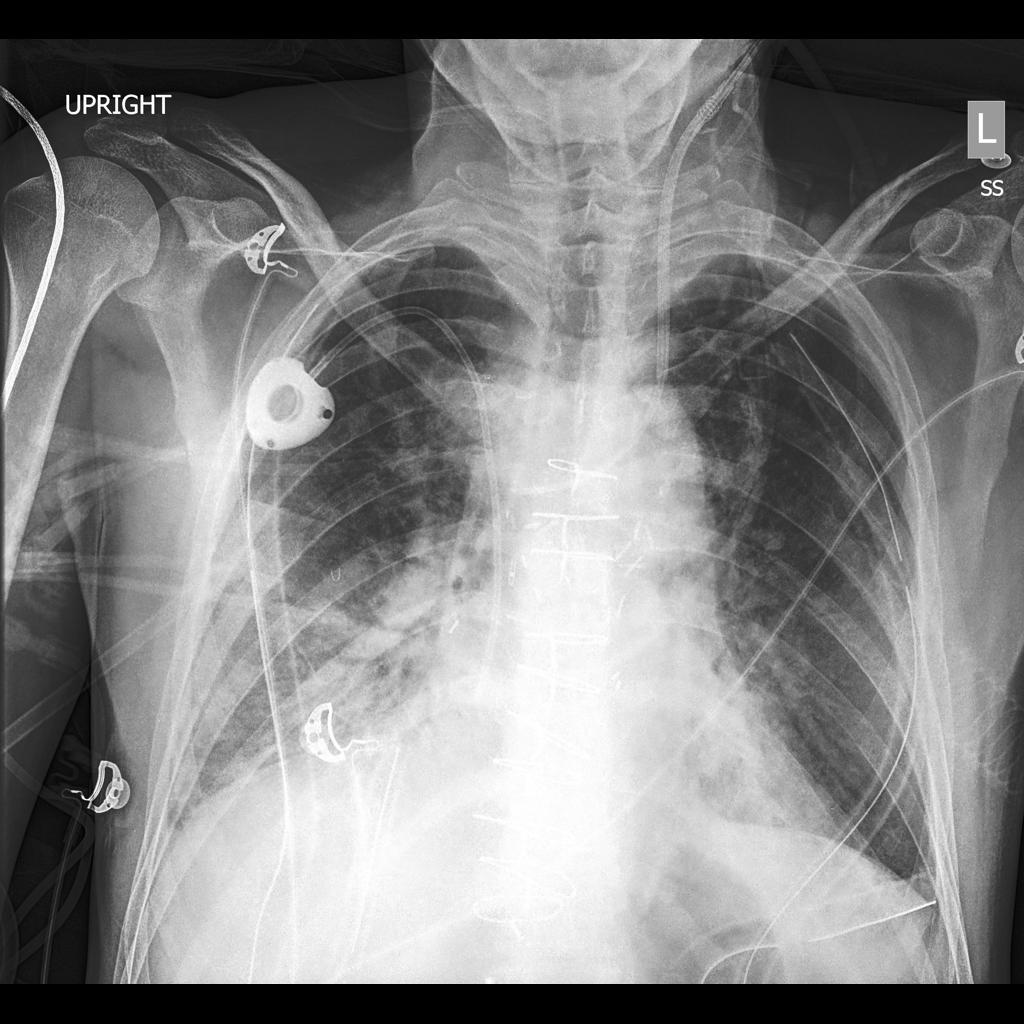

Diffusion models have recently gained significant traction due to their ability to generate high-fidelity and diverse images and videos conditioned on text prompts. In medicine, this application promises to address the critical challenge of data scarcity, a consequence of barriers in data sharing, stringent patient privacy regulations, and disparities in patient population and demographics. By generating realistic and varying medical 2D and 3D images, these models offer a rich, privacy-respecting resource for algorithmic training and research. To this end, we introduce MediSyn, a pair of instruction-tuned text-guided latent diffusion models with the ability to generate high-fidelity and diverse medical 2D and 3D images across specialties and modalities. Through established metrics, we show significant improvement in broad medical image and video synthesis guided by text prompts.

In this work, we focus on the ability of LDMs to generate novel datasets to overcome class imbalances traditionally associated with medical data, and potentially reduce the need for manual annotation of medical 2D and 3D data. We present MediSyn, a pair of text-guided latent diffusion models for broad medical 2D and 3D modality synthesis. To overcome the scarcity of labelled medical data, we leverage a vast corpus of more than 5 million image-caption pairs and 100,000 video-caption pairs collected from the public domain across numerous medical specialties, and integrate comprehensive natural language annotations to develop a pair of versatile diffusion models for the medical domain.

Our work, akin to Sagers et al. and Chambon et al. focuses on synthesizing multi-class medical datasets through text prompts. In their work, Chambon et al. adapt a pre-trained LDM, Stable Diffusion, on a corpus of chest x-rays (CXR) and their corresponding radiology reports to generate CXR displaying different disease states [29]. Similarly, Sagers et al. use DALL-E to synthesize skin lesions across all Fitzpatrick skin types [30].

Our findings demonstrate Medisyn’s remarkable ability to generate high-fidelity and diverse medical images, image sequences and volumetric scans across various medical subspecialties and imaging modalities. Other medical text-driven diffusion models, such as TauPETGen [42] for tau PET images and GenerateCT [43] for chest CT volumes, have proven successful in generating high-quality images that accurately depict anatomical features and clinical conditions. However, these models are constrained to a single imaging modality and anatomical region, thereby restricting their applicability. Moreover, they were trained on relatively small datasets sourced from a limited number of institutions, which could lead to more biased outputs. In contrast, Medisyn, having been trained on one of the largest publicly accessible medical image and video datasets to date, is equipped to synthesize data that cover numerous medical disciplines, population groups, and disease states. Leveraging our two models, we can synthesize new medical datasets as well as augment existing ones, potentially improving a wide array of medical machine learning tools, both general and specialized. Additionally, our models can minimize the need to repeatedly fine-tune on specific datasets for generating different imaging modalities, thus reducing computational costs for academic labs.